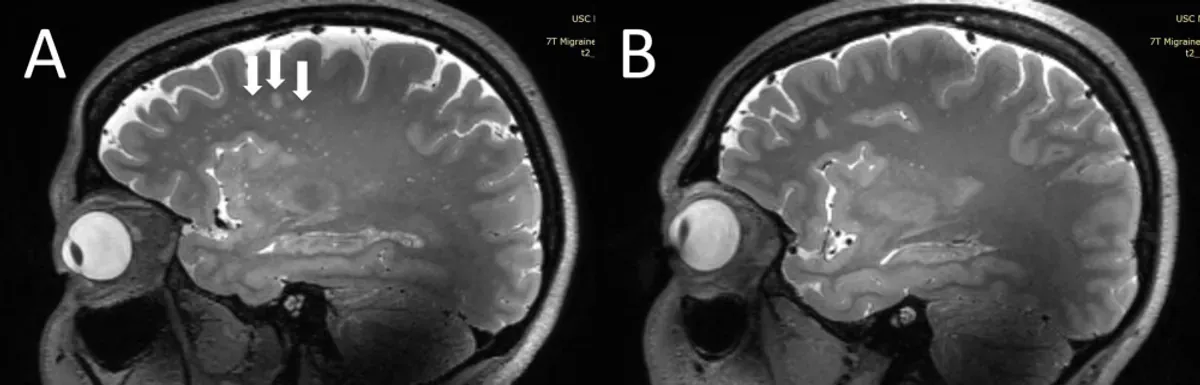

Стрелки указывают на гиперинтенсивность белого вещества, которая больше выражена в лобных долях при мигрени.

Стрелки указывают на гиперинтенсивность белого вещества, которая больше выражена в лобных долях при мигрени.© Wilson Xu

В ходе исследования на МРТ были просканированы десять человек с хронической мигренью, десять человек с эпизодической мигренью без ауры и пять здоровых  человек из контрольной группы. Исследователи искали отличия в периваскулярных пространствах — заполненных жидкостью промежутках, которые окружают кровеносные сосуды и очищают органы.

Помимо изменений в периваскулярных пространствах, учёные отслеживали поражение белого вещества, которое наблюдается только у людей, страдающих мигренью. Сканирование показало, что у страдающих от головных болей людей присутствуют значительные изменения в периваскулярных пространствах в пределах полуовального центра.

Как поясняют соавторы исследования, эти поражения белого вещества были в значительной степени связаны с наличием расширенных периваскулярных пространств. Это говорит о том, что изменения в периваскулярных пространствах приводят к поражению белого вещества, о чём ранее не было известно.